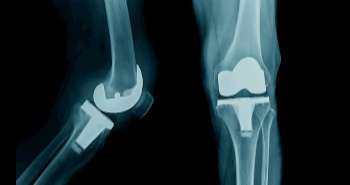

Are you at risk of developing rheumatoid arthritis?